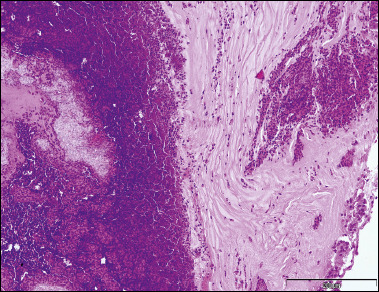

Results: The study included 26 patients. The most common forms of FRS treated by endoscopic sinus surgery was allergic FRS (AFRS). The fungus identification rate varied between entities, and was 72.2% in AFRS and 33.3% in fungal ball specimens. The common species seen in AFRS isolates were Cladosporium spp. (38.5% of isolated) and dematiaceous molds in the same percentage, while the remainder of the cultures were hyaline moulds. CT scan can be very helpful in diagnosing FRS and sometimes even in differentiating between different entities. Treatment of FRS should be tailored for each entity. Postoperative medical treatment in AFRS should consider potential advancements described in the literature.

Abstract Image